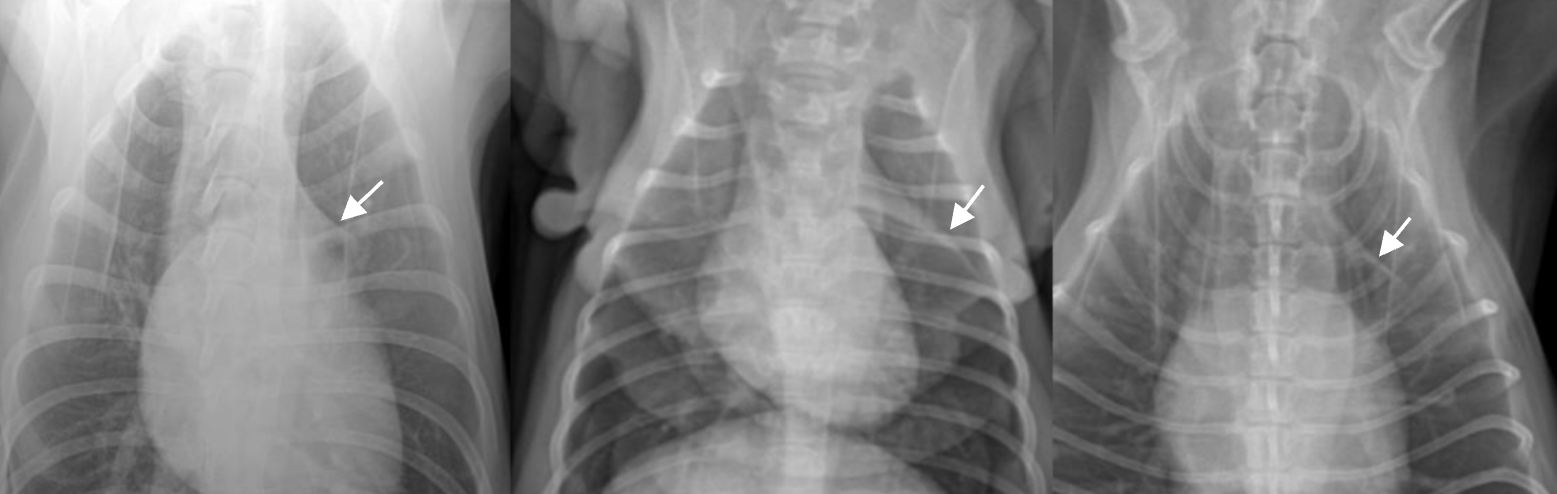

CCJ (costso-chondral junction) ![]() - 폐결절과 오인하지 않도록. - 닥스훈트에서는 꺾어서 관절하기 때문에 더 두드러짐. |